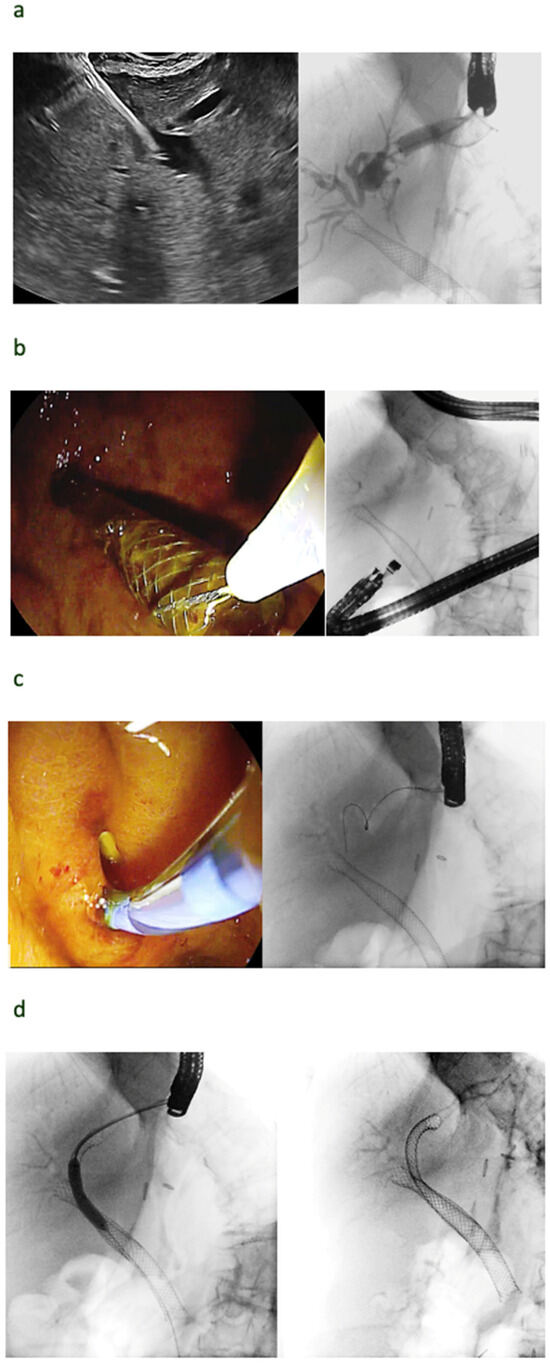

5. Rendezvous Techniques

5.1. Should Rendezvous Be Used First?

5.2. Which Rendezvous Route Should Be Used?